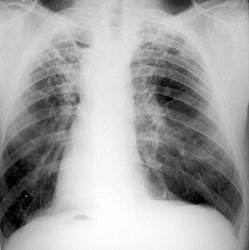

Diagnózis

A számos hatékony diagnosztikai módszerek összpontosított kimutatása TBC fertőzés a következők:

- Egy mellkas röntgen;

- Mellkas röntgen;

A legtöbb modern módszer – PCR. Ez a DNS diagnosztika, amikor egy mintát venni, a köpet a beteg. Az eredmény megtalálható után 3 nappal, a pontosság – 95-100%.